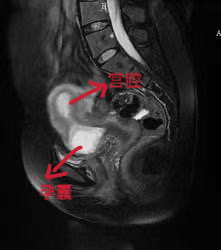

(盆腔核磁考虑:瘢痕子宫,瘢痕妊娠(Ⅲ型),临近子宫前壁肌层明显变薄,膀胱受压改变)